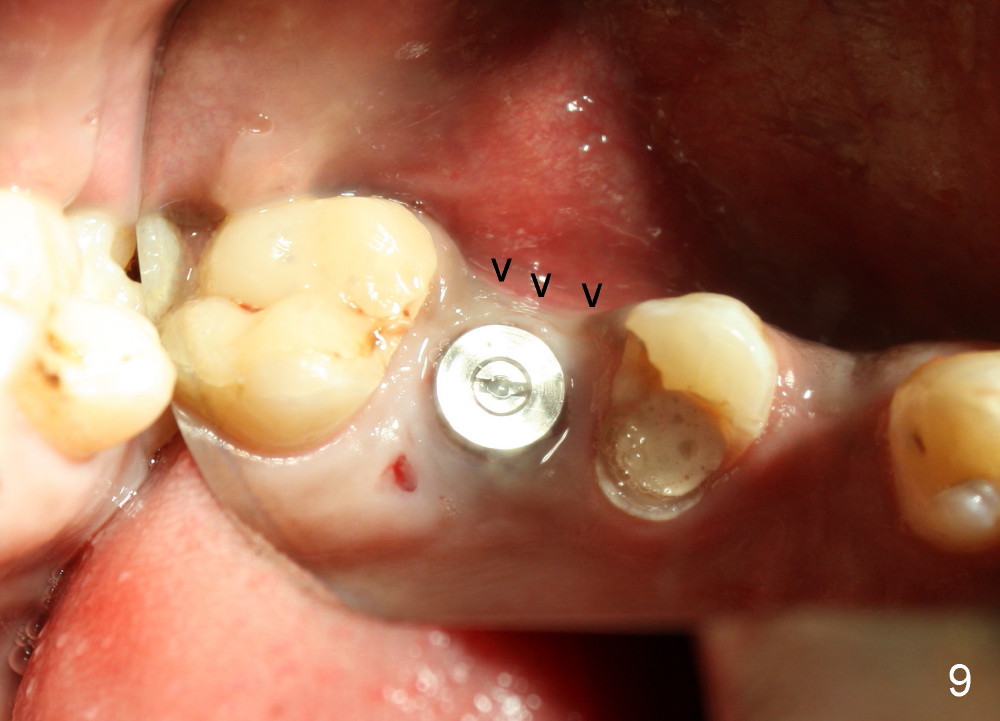

In addition to pain associated with dry socket, the buccal plate is atrophic 10 months post extraction (Fig.7 arrowheads, 1st case). A smaller implant (6x17 mm) is placed after bone expansion (Fig.8, bone appears to be soft). The buccal plate morphology improves immediately (Fig.9) and 6 days (Fig.10) post implantation and bone expansion. The patient returns for follow up 7 months postop; the implant appears to have osteointegrated (Fig.11). The implant has been restored for 3 months (09/11/2014).